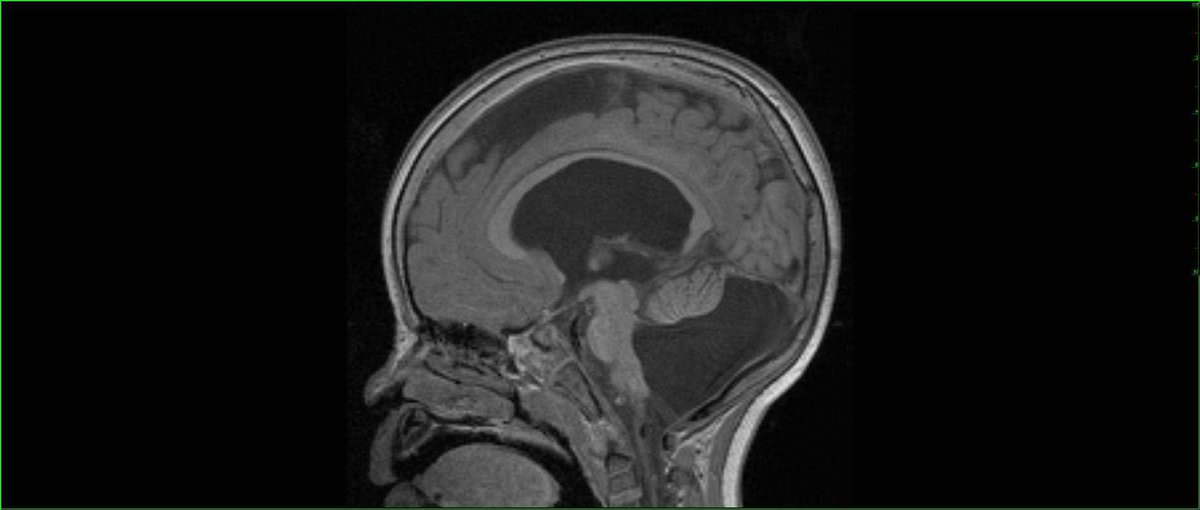

Денди уокера мрт

Денди уокера мрт 112 фотографий